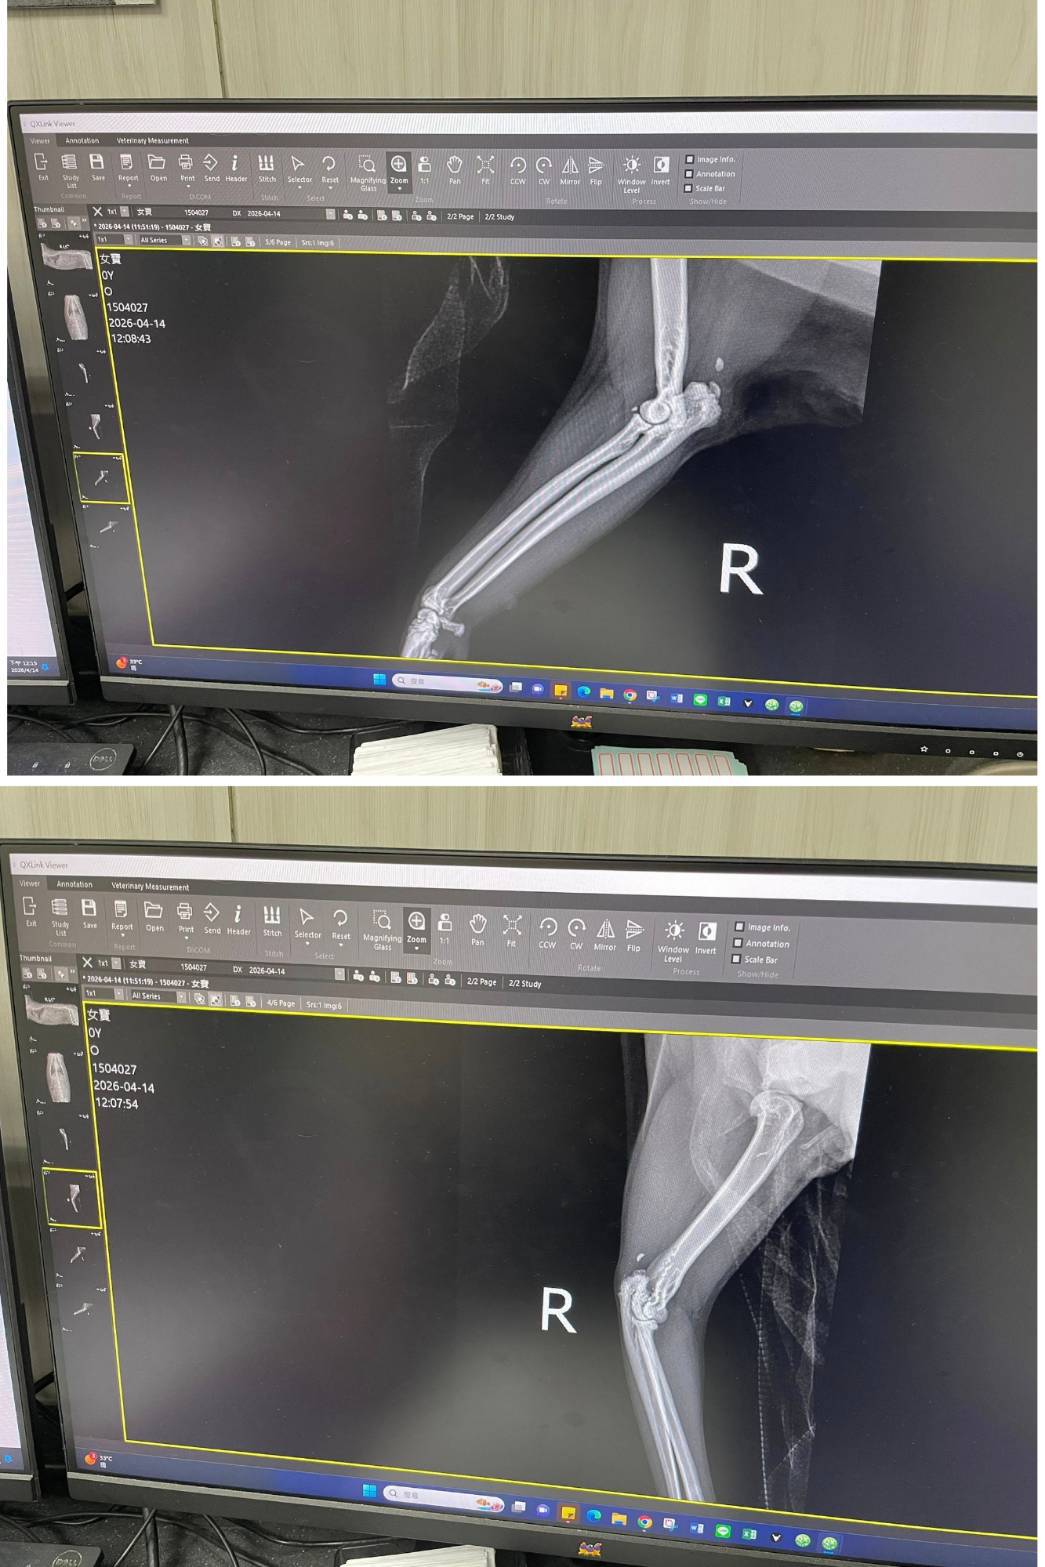

經X光檢查發現右前肢骨骼退化較嚴重,左邊也有一點骨骼退化;肺功能也是偏差;有牙周炎、牙齦萎縮所以齒根比較出來。X光有拍到兩顆東西,穿刺抹片檢查,淋巴細胞正常,淋巴結腫大。於醫院先點一錠除,並開立內用驅蟲藥,三個月後體外驅蟲需要再做一次。目前已於14日當日就醫後先行安置於協會幾日,因考量女寶年齡已大,汐止愛媽會帶回家中安置給女寶一個長久安穩的家。本筆醫助是女寶2026年4月14日於沐恩醫院看診的費用,包含血檢、X光、三合一、心臟快篩、皮膚抹片、一錠除滴劑及驅蟲藥。

右前肢比較嚴重左邊也有一點骨骼退化。